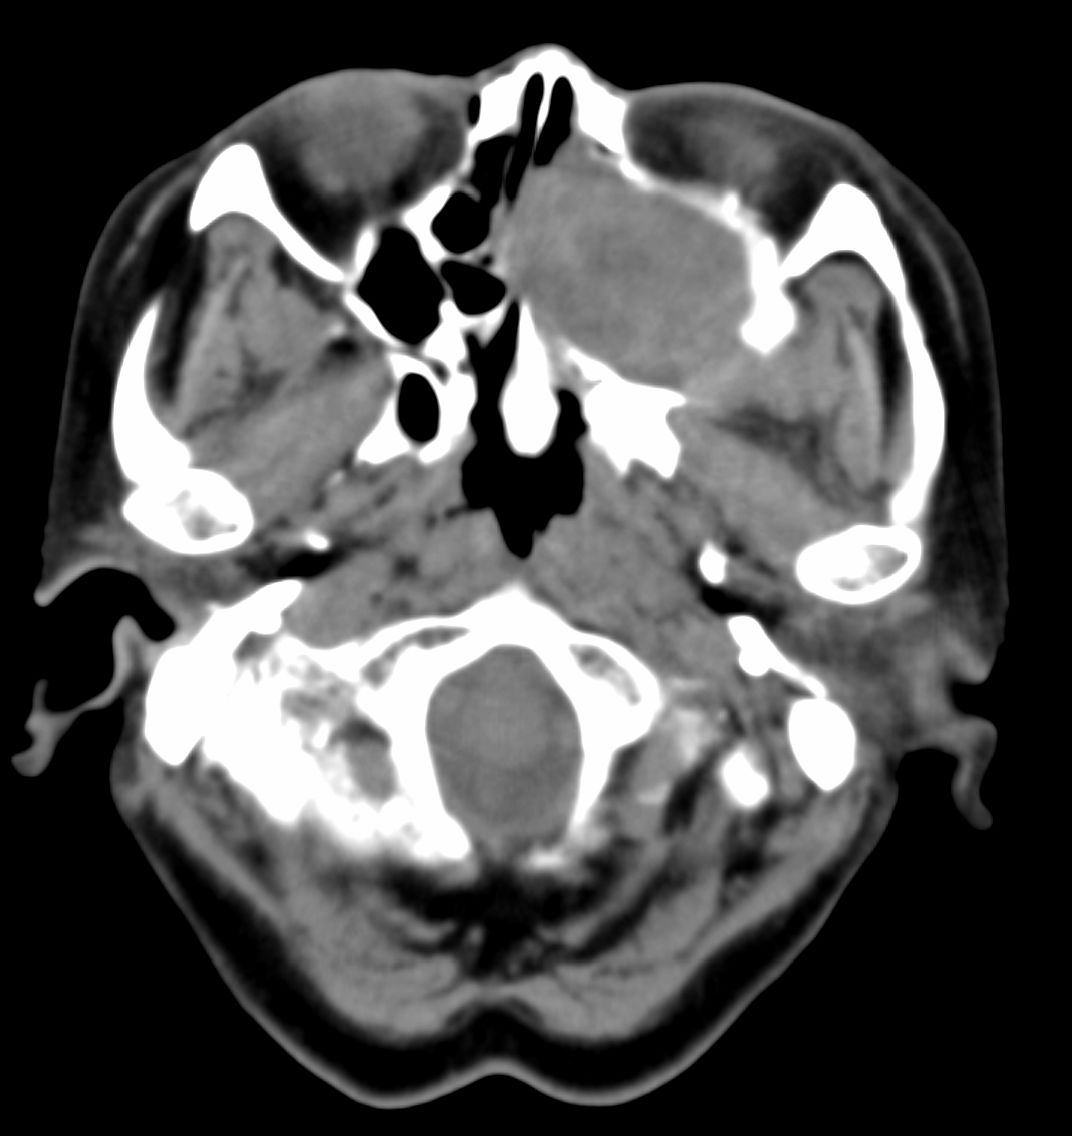

女,69岁。鼻出血2月多。(会诊病史就这样简单)鼻副窦ct检查如下:

左侧鼻腔及上颌窦见软组织块影,左侧上颌窦腔扩大,骨质吸收,右侧上颌窦见半圆形软组织密度影,鼻中隔向右侧弯曲,左侧鼻和鼻窦内翻型乳头状瘤可能性大,建议增强。

左侧上颌窦及鼻腔内见软组织密度影,其内密度不均匀,见斑片状高密度影,右侧上颌窦腔明显扩大,窦壁吸收变薄,鼻中隔右偏,右侧上颌窦见一半圆形软组织密度影,边界清楚,其内密度均匀。诊断,1、左侧鼻腔及上颌窦内翻乳头状瘤可能性大,上颌窦癌,息肉及霉菌性上颌窦炎待除外。2、右侧上颌窦粘膜下囊肿。

窦腔密度不均匀增高,无明显钙化征象,后外侧及内侧窦壁膨胀明显,局部破坏消失,筛窦受累及,但双侧对比发现左侧窦壁骨质有硬化增白现象,这可能是支持左侧霉菌性上颌窦炎的主要依据点。